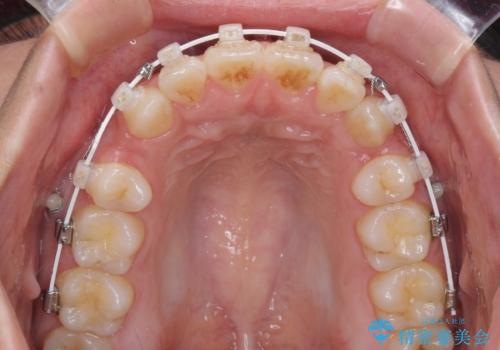

- 前歯のデコボコと口元の突出感を気にして来院された患者様です。

上下左右第一小臼歯4本を抜歯し、ワイヤー装置にて口元を引っ込めるよう矯正治療を行うこととしました。

非常にスムーズに歯列移動が行われ、当初は2-2.5年を予想していましたが、僅か1年4ヶ月で治療を終えることができました。